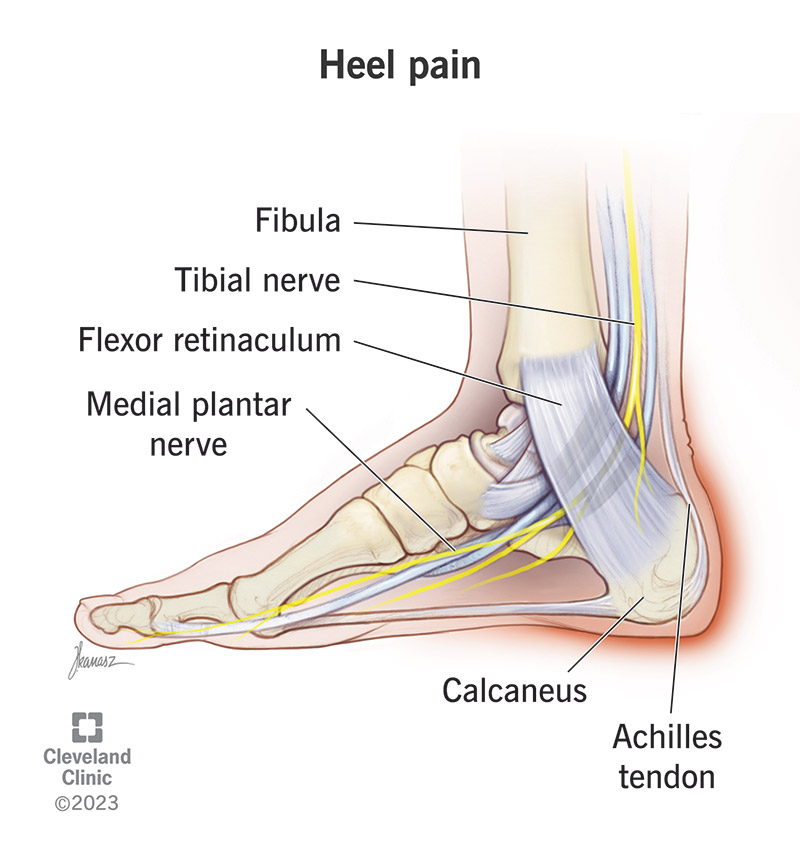

Heel Pain Causes Diagnosis Treatment